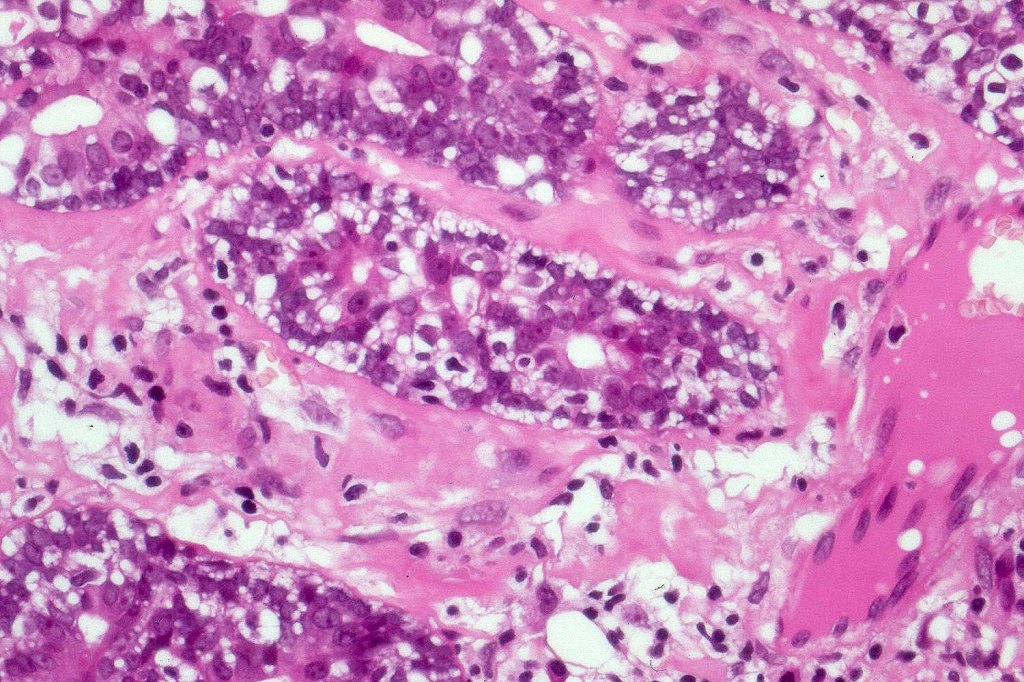

•Malignant component shows loss of dual cell population, increased mitotic activity, atypical mitoses & necrosis

•Perineural infiltration & LVI may be present

•Mixed spiradenocylindrocarcinoma

•Rarely carcinosarcoma has been documented